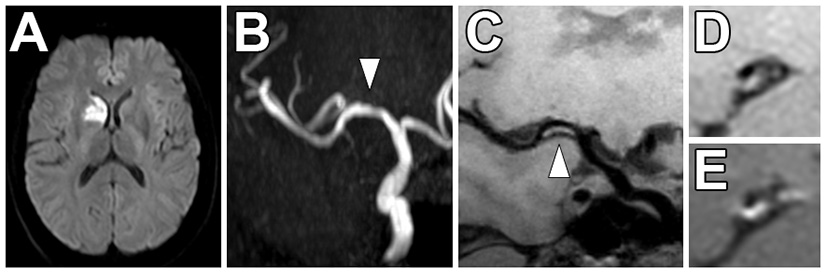

Multiple VW-MRI studies on intracranial atherosclerosis have shown that there is a higher prevalence of ipsilateral ischemic stroke in patients with contrast enhancing intracranial plaques independent of the degree of luminal stenosis (74–80). Figure 6 shows an example of an enhancing culprit plaque in a non-stenotic vessel that was felt to be the most likely source of a right basal ganglia ischemic stroke after a diagnostic work-up. VW-MRI studies with histological correlation propose contrast enhancement is a marker of inflammation and instability (70, 71). A meta-analysis pooling 990 circle of Willis vessel segments from 11 VW-MRI studies reported that it was more than seven times more likely to observe contrast enhancement of a culprit plaque in association with acute/subacute ischemia in the supplied vascular territory {OR of 7.4 [(95% CI, 3.4–16.4), p < 0.001]} (64), indicating this may be one of the stronger imaging biomarkers to detect culprit intracranial plaque. In the literature, definitions of focal/eccentric and circumferential vessel wall thickening detailed above are similar to the definitions of degrees of eccentric and circumferential enhancement.

Figure 6

Non-stenotic right middle cerebral artery enhancing culprit plaque. (A) A patient with a right basal ganglia acute infarct showed (B) mild luminal irregularity but no appreciable stenosis of the right middle cerebral artery on time-of-flight MRA imaging (arrowhead). (C) Precontrast VW-MRI showed eccentric wall thickening along the right M1 middle cerebral artery (arrowhead). (D) Precontrast and (E) postcontrast images in the orthogonal plane through the plaque shows eccentric wall thickening and enhancement of the culprit plaque, which likely caused the ischemic infarct.

There are few studies evaluating the use of intracranial VW-MRI specifically in the ESUS/CS population (Table 3). A 7 Tesla (T) VW-MRI study in 2020 by Fakih et al., evaluated 34 patients admitted to the stroke service with acute stroke of cryptogenic origin and unspecific arterial changes on CTA, MRA or DSA that did not meet a diagnosis of a specific vasculopathy. 7T VW-MRI led to the determination of a new stroke etiology in 28 of 34 patients, among which intracranial atherosclerosis was adjudicated as the stroke etiology in 25 of 28 patients. 7T VW-MRI identified culprit plaques as having significantly higher plaque-to-pituitary stalk contrast enhancement ratio, showed concentric morphology compared to non-culprit plaques, showed higher mean signal intensity, and higher contrast ratios compared to non-culprit plaques (p ≤ 0.001) (62). This study suggests 7T VW-MRI may be used to achieve a more accurate diagnosis of underlying intracranial atherosclerosis as a stroke etiology in a subset of stroke patients meeting criteria for cryptogenic stroke (Figure 7).

Figure 7

Comparison of 3 and 7 Tesla (T) VW-MRI for intracranial atherosclerosis. A patient with history of obesity, hyperlipidemia and hypertension and ischemic stroke underwent a (A) 7T TOF-MRA, which showed left M1 middle cerebral artery severe stenosis (arrowhead). (B) 7T MRI axial T1 SPACE post-gadolinium (0.5 mm isotropic resolution) image clearly delineates arterial wall thickening and avid vessel wall enhancement in the region of stenosis (arrowhead). (C) The same patient was imaged 18 days later on a 3T MRI (T1 SPACE post-gadolinium, 0.8 × 0.8 × 1.0 mm) to assess the stenosis (arrowhead). The 7T VW-MRI shows improved conspicuity and delineation of the margins of the arterial wall compared to the 3T, an advantage of the higher magnet strength due to the higher signal to noise leveraged for higher spatial resolution and soft tissue contrast.